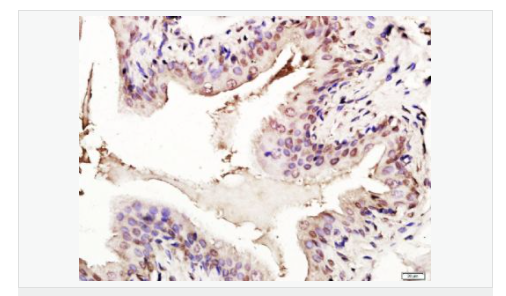

| 產(chǎn)品應(yīng)用 | WB=1:1000-2000 ELISA=1:1000-5000 IHC-P=1:100-500 IHC-F=1:100-500 Flow-Cyt=1ug/Test ICC=1:100-500 IF=1:100-500 (石蠟切片需做抗原修復(fù)) not yet tested in other applications. optimal dilutions/concentrations should be determined by the end user. |

| 細(xì)胞定位 | 細(xì)胞核 細(xì)胞漿 |